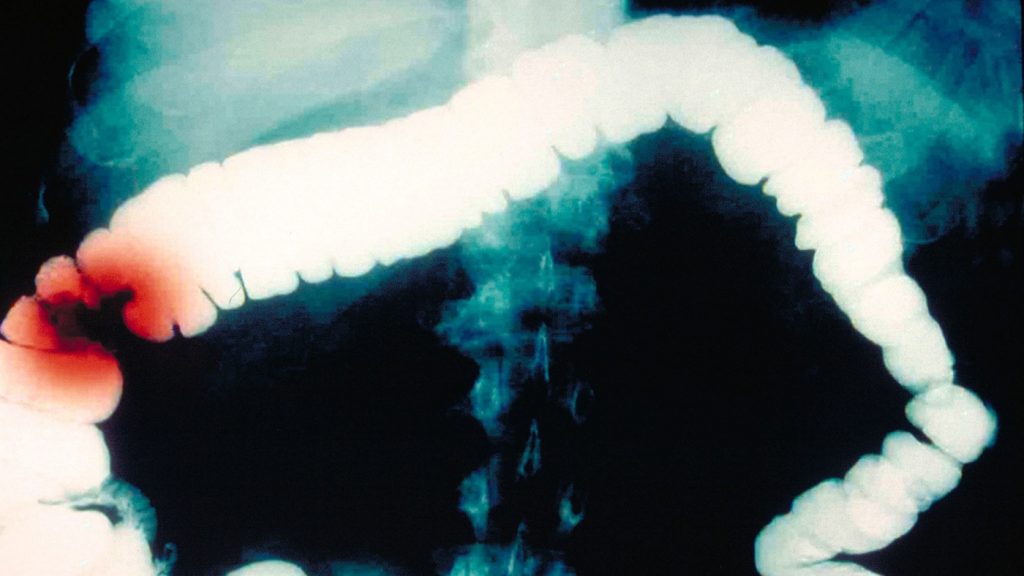

سرطان کولون